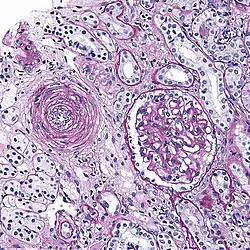

Hyaline arteriolosclerosis

Also arterial hyalinosis and arteriolar hyalinosis refers to thickening of the walls of arterioles by the deposits that appear as homogeneous pink hyaline material in routine staining.[3] It is a type of arteriolosclerosis, which refers to thickening of the arteriolar wall and is part of the aging process.[4]

It is often seen in the context of kidney pathology.[4][8][9] In hypertension only the afferent arteriole is affected, while in diabetes mellitus, both the afferent and efferent arteriole are affected.[8][9] It is also seen in retina and brain,[10] where retinal infarcts and small brain infarcts, or lacunes can occur.

Hyperplastic arteriolosclerosis

This is a type of arteriolosclerosis involving a narrowed lumen.[4] The term "onion-skin" is sometimes used to describe this form of blood vessel[14] with thickened concentric smooth muscle cell layer and thickened, duplicated basement membrane. In malignant hypertension these hyperplastic changes are often accompanied by fibrinoid necrosis of the arterial intima and media. These changes are most prominent in the kidney and can lead to ischemia and acute kidney failure. In the brain, a small cavity called a lacune is an ischemic cavity that can arise due to brain necrosis, due to arteriolosclerosis.[15][16]